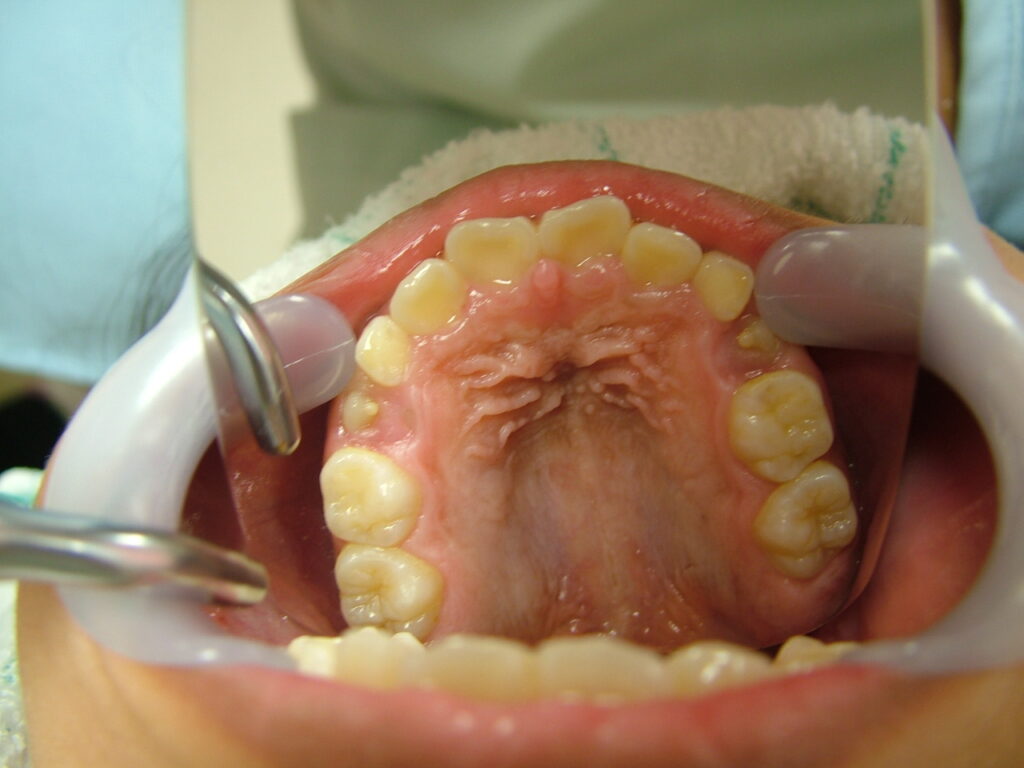

治療後2年

最後に高校1年の時に下顎前歯叢生(凸凹)予防のため、下顎埋伏親知らずの抜歯を行いました。後は、虫歯や歯肉炎にならないように、自己管理頑張ってください。